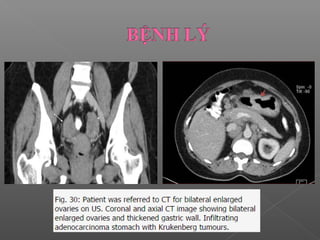

 Xuất hiện như một tổn thương ngoài dạ dày

U Krukenberg của buồng trứng  ung thư dạ dày

 Xuất hiệnnhư một tổn thương ngoài dạ dày U Krukenberg của buồng trứng  ung thư dạ dày Khí trong ổ bụng  thủng ổ loét Áp xe gan  do thủng dạ dày Viêm ruột thừa…